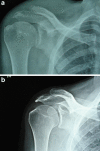

Methods: We performed a retrospective analysis on 14 patients with tuberculosis of the tendon-bone junction. Patients presenting with a sinus with or without presence of radiological evidence of bone destruction around the enthesis, and pain unresponsive to a trial of analgesics and physical therapy, were evaluated by closed or open biopsy for tuberculosis. A staging system is proposed for biopsy-proven tuberculosis of the enthesis.

Results: Between 2006 and 2010, we treated 14 patients with tuberculosis of the tendon-bone junction. Biopsy-proven cases of tuberculosis of the enthesis were administered anti-tubercular drugs for a period of one year. Sequestrectomy was performed in advanced lesions. The tendon-bone junction was rested until the features of its healing were clinically evident. The patients aged between 18 and 52 years were followed up for an average of 1.7 years after cessation of anti-tubercular drug therapy. They responded favourably, and none had recurrence of the disease.